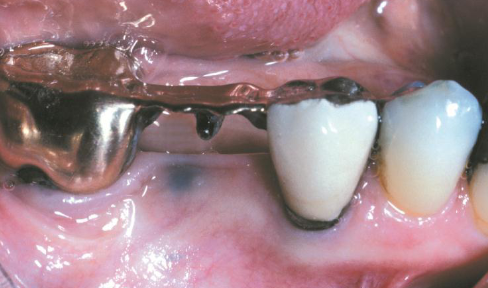

kaposi sarcoma

AIDS related vascular malignant neoplasm